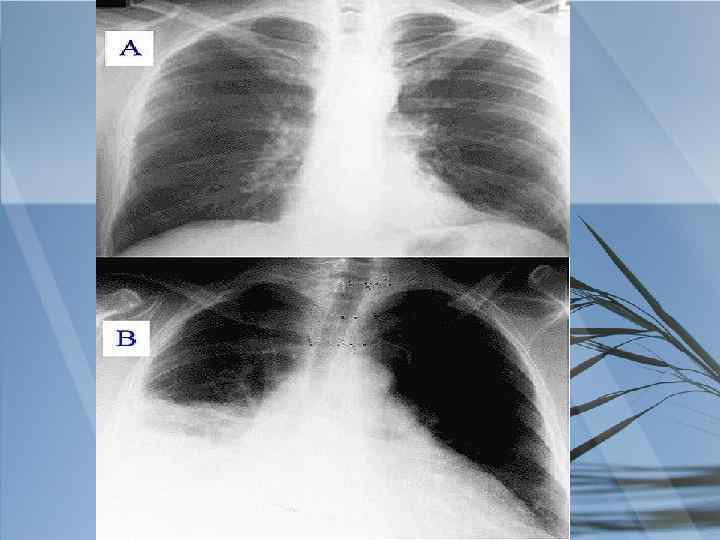

Инструментальные исследования: 1. Рентгенография грудной клетки в 2 -х проекциях. Позволит по форме затемнения уточнить диагноз пневмонии, оценить корни легких и не пораженную ткань легкого. 2. Фибробронхоскопия. Назначаем для выявления заинтересованности трахеи и главных бронхов в патологическом процессе. 3. ЭКГ

Результаты инструментальных исследований: 1. Рентгенография грудной клетки от 16. 4. 2010 Заключение: Выпот в плевральную полость. Инфильтрат справа. 2. ЭКГ от 17. 4. 2010 Заключение: ритм синусовый, ЧСС – 80 уд. /мин. , сдвиг электрической оси влево.

Анализируя весь симптомокомплекс у больного, то есть жалобы на постоянные, интенсивные, колющие боли в правой половине грудной клетки, усиливающиеся при дыхании, пальпации и кашле, кашель с выделением слизистой мокроты, слабость, одышку смешанного характера и повышение температуры тела; данные из анамнеза заболевания: резкое развитие всех симптомов, высокая лихорадка (39(С), появления слабости; данные объективного исследования: уменьшение подвижности нижнего края правого легкого, притупление перкуторного звука справа в нижнем отделе, появление жёсткого дыхания и наличие влажных мелкопузырчатых хрипов; данные лабораторно-инструментальных исследований: наличие в крови лейкоцитоза(15, 3*10(9/л) с преобладанием в лейкоцитарной формуле палочкоядерных, при рентгенологическом исследовании грудной клетки обнаружение инфильтрации в нижней доле правого легкого,